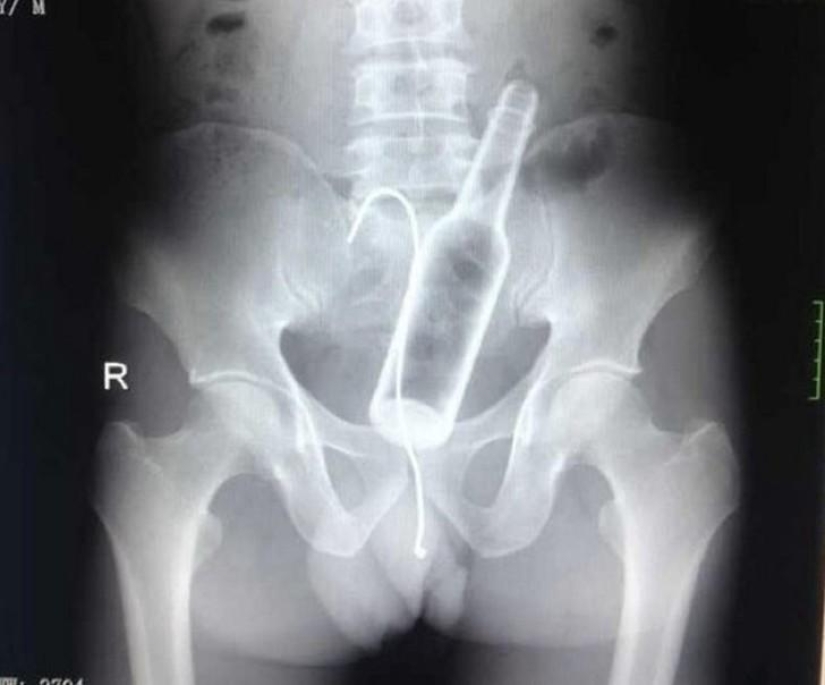

Bottle.